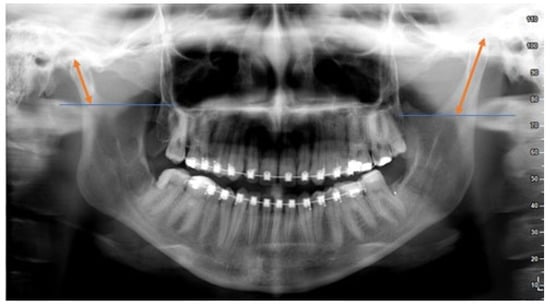

M—maxillary bones; low downward position of the maxilla on the affected side. Maxillary compensatory down growth = with or without maxillary cant deviated horizontal (transverse) occlusal plane (Figure 3), also manifested as the asymmetrical position of part of the maxillary bone with or without sinus floor;

Figure 3. Maxillary compensatory down growth on the affected side.